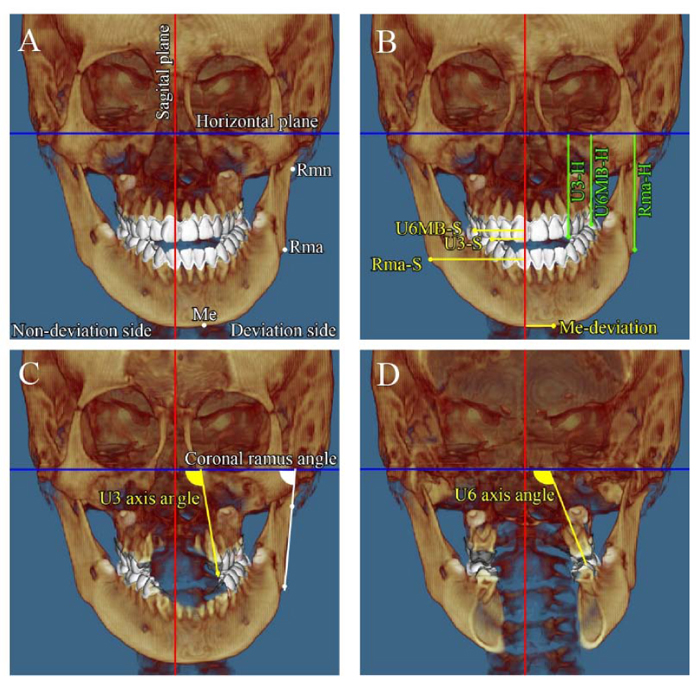

Panoramic radiography showed no horizontal or vertical bone loss and normal root length (Fig. 2). The cephalometric assessment showed a skeletal class I relationship (ANB angle, 3.2°) (Table 1) with a high mandibular plane angle (FMA, 35°) and occlusal plane angle (Occ plane to FH, 15.0°). The mandibular and maxillary incisor inclinations were normal (FMIA, 56.2°; U1-FH, 113.6°). Computed tomography (CT) imaging showed marked menton deviation to the left (13.5 mm) (Fig. 3 and Table 2) and dental asymmetry associated with occlusal plane cant (bilateral differences in tooth height: U3-H, 0.9 mm; U6MB-H, 3.3 mm). In addition, the bilateral differences in coronal ramus angle (coronal ramus angle, 10.3°) and ramus position (Rma-S, 13.6 mm) were significant [15].

The intrusion of the maxillary right dentition (N-side: U3-H 0.4 mm canine intrusion, U6MB 1 mm molar intrusion) and extrusion of the left dentition (D-side: U3-H 0.6 mm canine extrusion, U6MB 2.1 mm molar extrusion) resolved occlusal plane canting, contributing to facial asymmetry. Significant improvements were also seen in coronal ramus angle (N-side 78.0°, D-side 80.9°) and ramus position (Rma-H: N-side 55.9 mm, D-side 54.5 mm) after orthognathic surgery with BSSO.

Facial asymmetry has a marked influence on physical appearance, and numerous dysmorphic syndromes are associated with severe mandibular asymmetry [16]. Such cases have multifactorial problems, including skeletal deformation and dental compensation [3, 4, 16]. Therefore, accurate evaluation of facial asymmetry by three-dimensional analysis with CT is required to achieve successful treatment outcomes [6, 17]. In this case, detailed CT imaging showed severe facial asymmetry associated with occlusal plane cant (bilateral differences in tooth height; U3-H, 0.9 mm; U6MB-H, 3.3 mm), transverse dental compensation (bilateral difference in U6 axis angle: 20.3°), and mandibular deformation. Two-jaw orthognathic surgical approaches are usually used to treat facial asymmetry with severe maxillary deformation, including dental asymmetry [6–8]. As maxillary deformation in the present case was limited to a mildly canted occlusal plane and transverse dental compensation, a one-jaw surgery approach (BSSO) was applied to correct the mandibular facial asymmetry. The canted occlusal plane and transverse dental compensation were resolved by a combination of a fixed appliance with miniscrew implant anchorage during presurgical orthodontic treatment. A satisfactory treatment outcome with a symmetrical facial appearance was achieved.